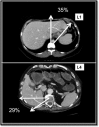

Methods: Fifty computed tomography (CT) scans obtained in subjects with normal liver were studied. Four CT scan levels were preselected: level 1 passed by the upper part of the hepatic veins; level 2 passed by the left portal vein branch division; level 3 passed by the right portal vein branch division, and level 4 passed by the gallbladder bed. Left and right tangent lines passing the liver edges were drawn and joined to the centre of the vertebra defining the TL angle. Two lines through, respectively, the plane of the middle hepatic vein and the left portal branches determined the angles of the RL, LL and LLS. Volumetric and angulometric data obtained on levels 2 and 3 in 50 different subjects were compared.

Results: Level 2 CT scans represented the most accurate way of obtaining angulometric measurements. The mean ± standard deviation (SD) angles of the TL and LL were 134 ± 12 ° and 55 ± 12 °, respectively. The mean ± SD percentages of the TL represented by the LL in angulometry and volumetry were 38 ± 7% and 36 ± 6%, respectively (non-significant difference). The mean ± SD percentages of the TL represented by the LLS in angulometry and volumetry were 25 ± 4% and 20 ± 3%, respectively (P < 0.05). The mean ± SD overestimation of the percentage of the TL represented by the LLS in angulometry was 2.7 ± 7.0%.